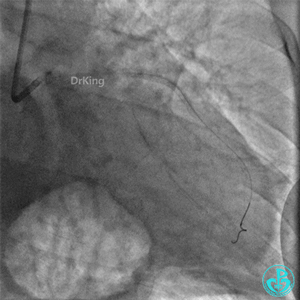

左股入路JR 4.0指引导管翻山造影,右侧股动脉穿刺点局部造影剂外漏。

翻山5.0×8mm球囊局部封堵破口处加术者用手局部压迫。

球囊封堵30分钟后造影,破口局部无渗漏,下台观察。